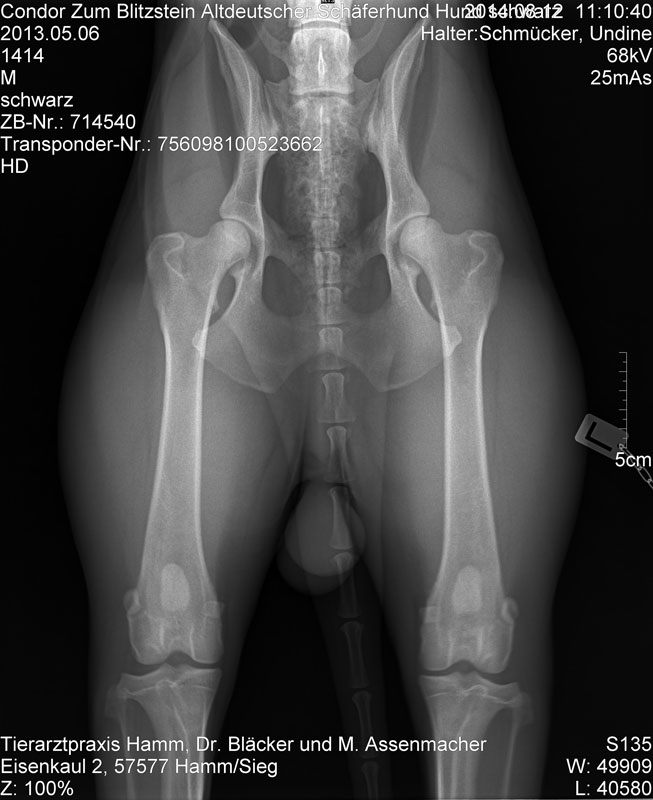

HD-ED Aufnahme  von Condor`s Hüfte vom 12.08.2014

HD normal, kein ED

Hüfte